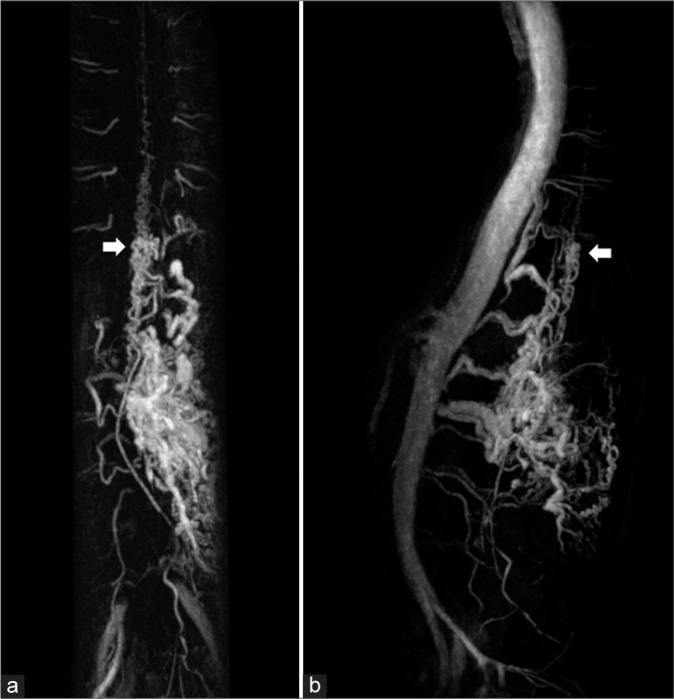

A 42-year-old woman presented with intermittent low back pain for 6 months. Magnetic resonance imaging of the thoracolumbar spine incidentally found clusters of spinal vascular malformations involving spinal cord, vertebral bodies, epidural space, and paraspinal muscles. There was no sign of venous congestion. Magnetic resonance angiography and spinal angiography revealed intradural spinal cord arteriovenous malformation (SCAVM) at the level of T10-11 and extradural high-flow osseous arteriovenous fistula. Due to asymptomatic SAMS and a high risk of anterior spinal arterial compromise during treatment, conservative treatment was considered in our patient. Spinal angiography obtained 8 years after initial angiography demonstrated significant regression of extradural component of SAMS and stable intradural SCAVM.

一名42岁女性出现间歇性腰痛6个月。胸腰椎磁共振成像偶然发现累及脊髓、椎体、硬膜外间隙和椎旁肌肉的脊髓血管畸形簇。无静脉淤血迹象。磁共振血管造影和脊髓血管造影显示T10 - 11水平的硬脊膜内脊髓动静脉畸形(SCAVM)和硬膜外高流量骨动静脉瘘。由于患者为无症状性SAMS且治疗期间存在脊髓前动脉受损的高风险,我们的患者考虑采取保守治疗。初次血管造影8年后进行的脊髓血管造影显示SAMS的硬膜外成分显著消退,硬脊膜内SCAVM稳定。